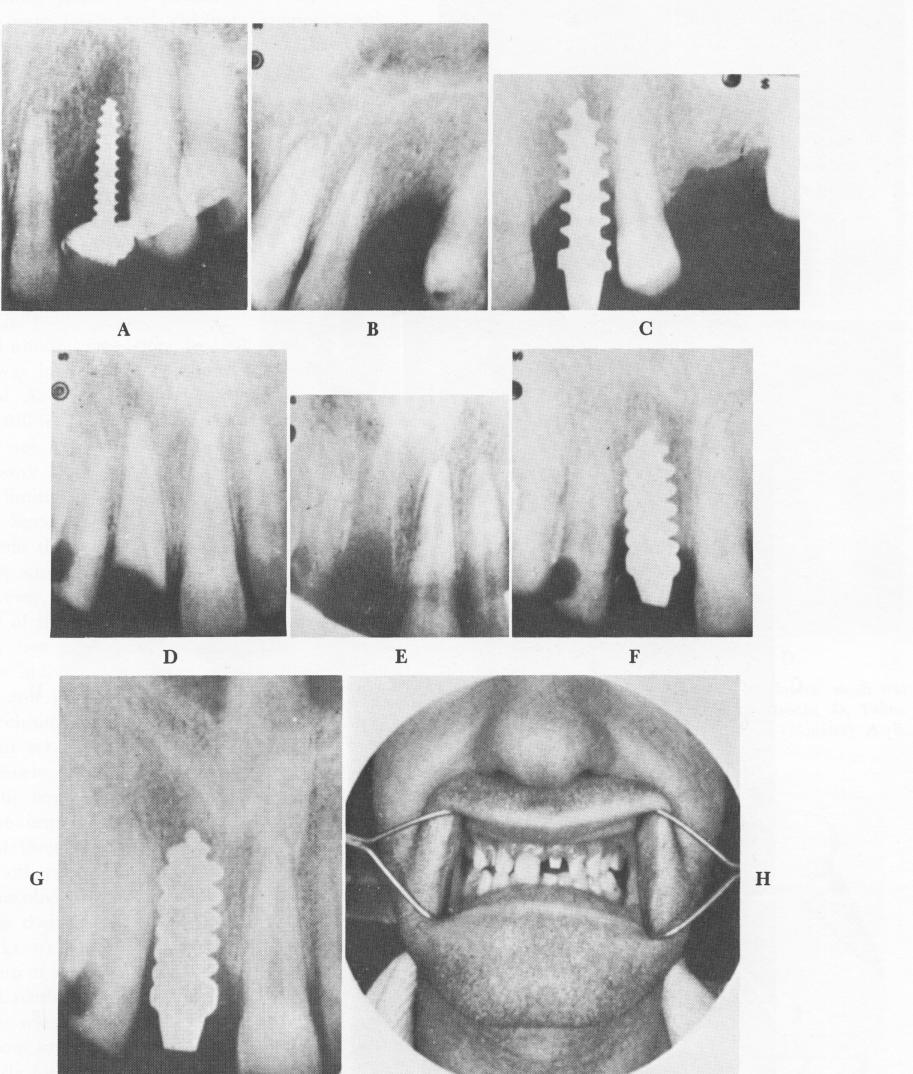

Fig. 5-8. Two kinds of screw implants were used in this Strock case. A, The first implant, which was quickly removed because of extreme looseness. B, The edentulous area after the implant was removed. C, Another implant inserted in the same site. D and E, A central incisor to be replaced by a new type of post. F to H, Results obtained with this post. The post remained in place up to 6 rnonths later. However, little or no bone repair is seen. (From Strock, A. E.: Experimental work on a method for the replacement of missing teeth by direct implantation of a metal support into the alveolus, Amer. J. Orthodont. 25:467-472, 1939.)

1 Removal of loose Strock endosseous implant from maxilla